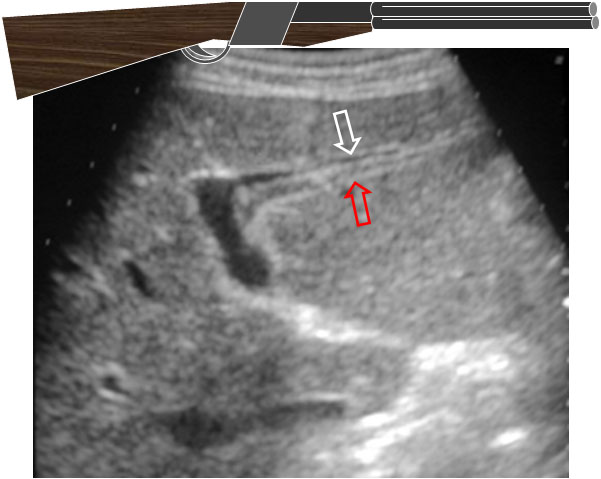

SIGNO DEL DOBLE ARCOdoble arcoSigno ecográfico de colelitiasis. Consiste en la visualización de dos líneas arqueadas paralelas ecogénicas entre las que queda un espacio anecoico; existe sombra acústica distal. El arco periférico corresponde a la pared vesicular (flecha blanca) mientras que el segundo arco pertenece al borde del cálculo (flecha roja). El espacio anecoico que queda entre ambos corresponde a la luz vesicular.